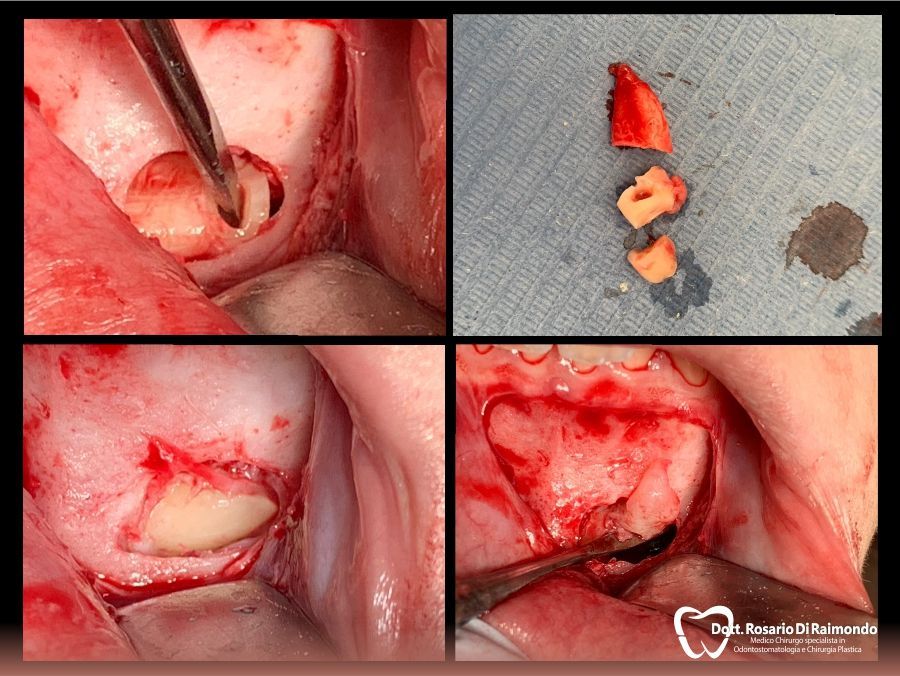

Estrazione del dente del giudizio

La rimozione del dente del giudizio, tecnicamente chiamata disodontiasi degli ottavi, è uno dei trattamenti principali della chirurgia odontoiatrica. Le indicazioni per l’estrazione del dente del giudizio sono molteplici: terzo molare con insufficiente spazio per erompere completamente o posto in una posizione anomala (comunemente detto dai pazienti “dente del giudizio storto”), indicazione da parte dell’ortodontista per l’allineamento dei denti in mancanza di spazio nelle arcate dentarie, presenza di profonde carie del dente del giudizio e infine estrazione strategica per evitare problemi nel molare adiacente.

Germectomie del dente del giudizio

L’estrazione dei denti del giudizio quando ancora non hanno completato il loro sviluppo, quindi in età prepuberale, è una indicazione corretta, perché non essendo il dente ancora completamente formato, permette al dentista di ridurre i tempi dell’intervento e quindi i conseguenti disagi al piccolo paziente.

Casi Trattati

Di seguito riportiamo alcune fotografie di casi esplicativi di Chirurgia Orale.